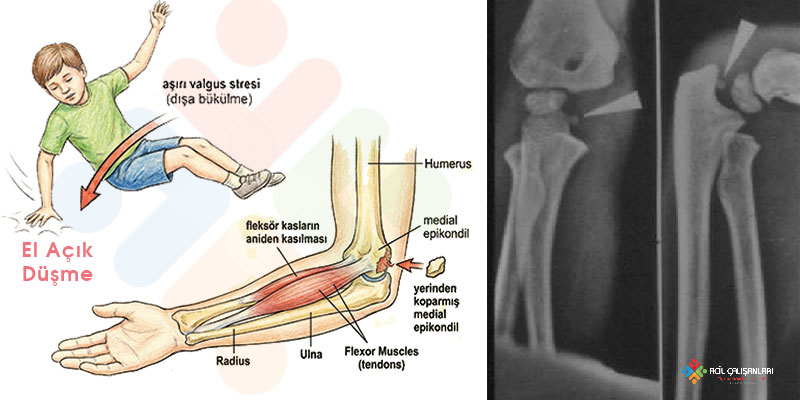

Avülsiyon Mekanizması (en sık)

Valgus stres + fleksör-pronatör kas grubunun güçlü çekmesi

PATOFİZYOLOJİ

Valgus stres altında medial epikondil apofizi, epifizden kopma tarzında ayrılır.

Dirsek çıkığı eşlik ediyorsa fragment eklem içine sıkışabilir → redüksiyon başarısız olur.